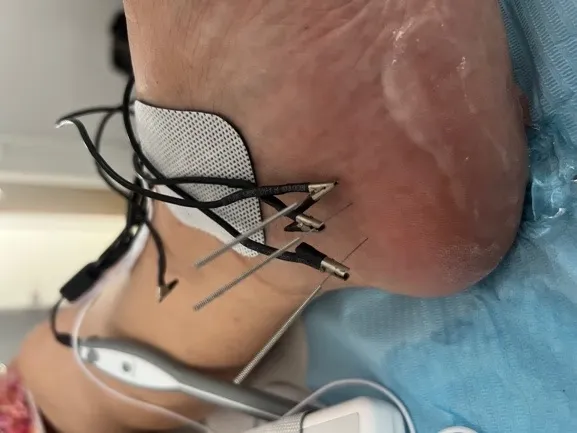

Neuromodulación Percutánea Ecoguiada

También ofrecemos electrólisis percutánea para casos de fascitis plantar muy resistentes al tratamiento.

- Neuromodulación - Técnica invasiva de última generación

Electrólisis Percutánea

Electrólisis percutánea ecoguiada para tendinopatías y lesiones musculoesqueléticas crónicas.